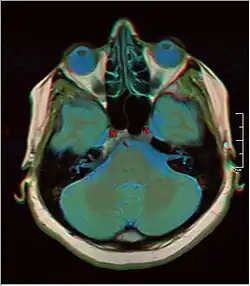

![]() Cross-sectional T1-weighted MRI of a healthy human brain acquired with an ultra high-field MR of 7 Tesla field strength | |

A number of different imaging modalities or sequences can be used with imaging the nervous system:

- T1-weighted (T1W) images: Cerebrospinal fluid is dark. T1-weighted images are useful for visualizing normal anatomy.